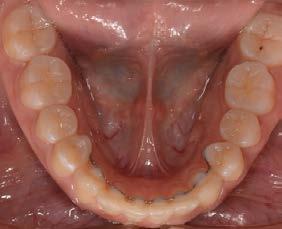

Objetivo: presentar un caso clínico de paciente con mordida abierta anterior, clase II y deglución atípica tratada con aparatología fija ortodóntica.

Caso clínico: paciente femenino de 19 años, patrón dolicofacial, perfil convexo, clase II esqueletal debido a una retrusión mandibular, mordida abierta anterior esqueletal, clase II molar, clase canina no establecida por mordida abierta, apiñamiento severo superior e inferior y deglución atípica.

Resultados: obtención de una clase canina I y clase molar II funcional, se corrigieron las sobremordidas horizontal y vertical, y se logró la coincidencia de líneas medias facial y dental. El manejo de la mordida abierta anterior se llevó a cabo por medio de la corrección del hábito de deglución atípica con la ayuda de spikes de resina, elásticos intermaxilares y arcos utility, y se obtuvieron buenos resultados estéticos, dentales y funcionales.